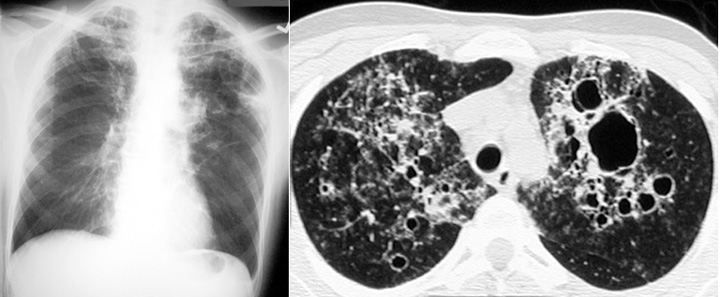

Pneumocystis Carinii pneumonia

This CT of a patient with AIDS shows numerous thin walled cavitary upper lobe lesions, residual of PCP pneumonia.